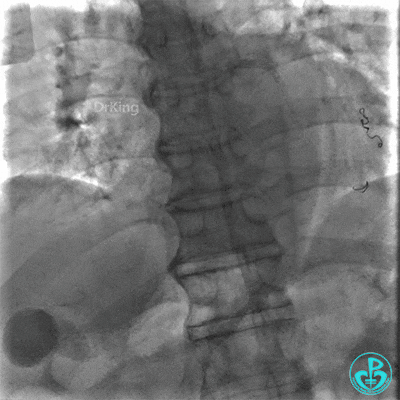

右冠脉支架通畅无狭窄,右冠脉给前降支远端提供逆向侧支循环。

EBU指引导管左冠脉造影显示粗大前降支中段闭塞,闭塞段近端有对角支发出,前降支同侧逆向显影,闭塞段不长。